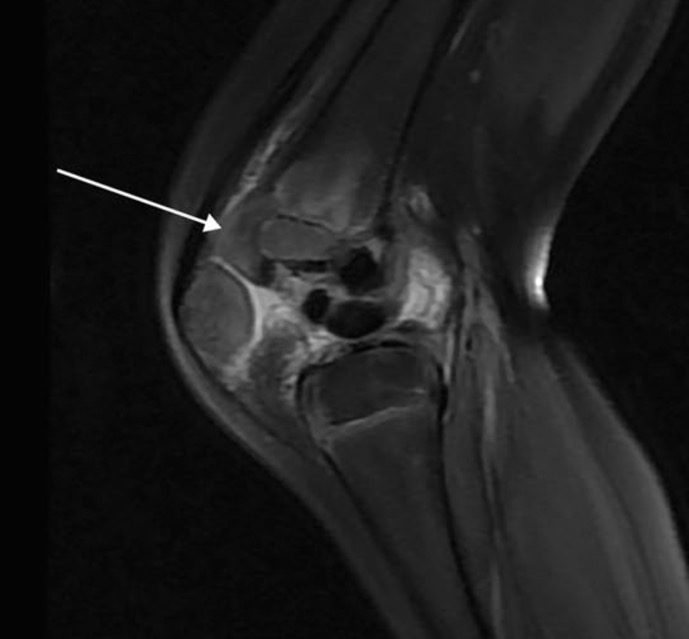

calcinose tumorale

Affection rare

Dépôt de masses de sels de calcium dans les tissus mous, souvent près des articulations

Ressemblent à des tumeurs mais NON cancéreuses

=> gêne, douleur, limitation

DD: 1. Infection ostéoarticulaire (absence d'abcès)

2. Chondrodysplasie métaphysaire (contour métaphysaire normal sans évasement)

TRT: excision chirurgicale complète des masses